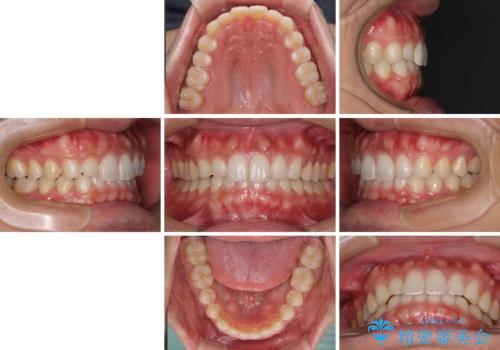

- 患者様

- 20代男性

- 矯正装置

- インビザライン

- 治療期間

- 1年5ヶ月

- 治療計画

- 上下の前歯の隙間を気にして来院された患者様です。

インビザラインを用い、上下歯列のスペースを閉じていくこととしました。

銀行にお勤めのため、突然の転勤により通院が大変な状況となりましたが、インビザラインであれば2-3ヶ月に1度を目安に来院いただき、無事に治療を終えることができました。